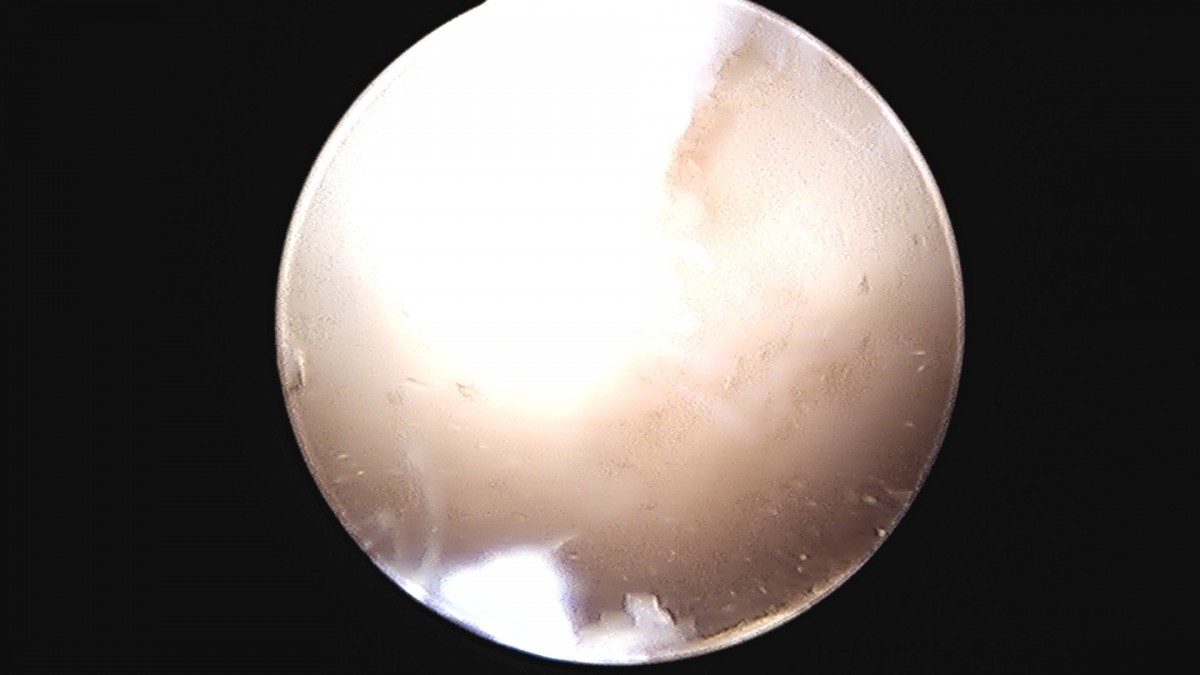

정지영원장님 발목 변연절제술 권공O 환자

작성자 최고관리자 댓글 0건 조회 743회 작성일 25-09-16 17:04